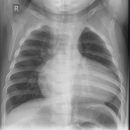

Thorax seitlich

Darstellung der Sagittalebene des Thorax und der Brustorgane, anliegende Seite richtet sich nach dem Befund, ohne spezielle Angabe wird generell links anliegend geröntgt. Atemphase: maximale Inspiration.

Wirbelsäule rein seitlich, Sternum seitlich getroffen, komplette Darstellung der Lunge von Lungenspitze bis einschließlich Rippen-Zwerchfell-Winkel. Die Mediastinalstrukturen und retrocardialen Gefäßabschnitte sind gut differenzierbar und der Herzhinterrand scharf abgrenzbar.